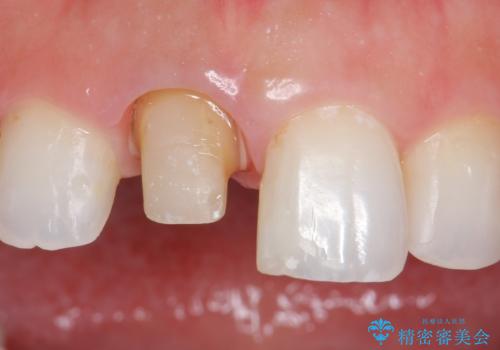

- 右上1の前歯の見た目が気になるので被せ物をやり替えたいといらっしゃった方の症例です。

再根管治療終了後、オールセラミッククラウン(スペシャル)によって隣在歯に合わせた補綴を行いました。